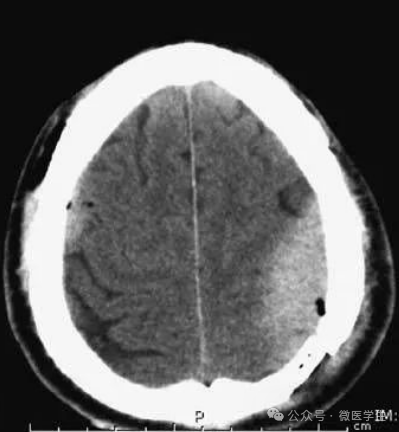

高血压性脑出血:

- 自发性出血;

- 继发于长期高血压及慢性血管病;

- 常见于基底节区、丘脑、脑桥、小脑。

A:占位效应,相邻脑沟、脑池消失;

F:脑出血破入四脑室。

▲

钩回疝:

是当代偿机制不能适应占位性病变时的结果。

基底节区大量高血压性脑出血,破入脑室及蛛网膜下腔,周围水肿,脑干周围空间消失;脑干出血、脑积水。